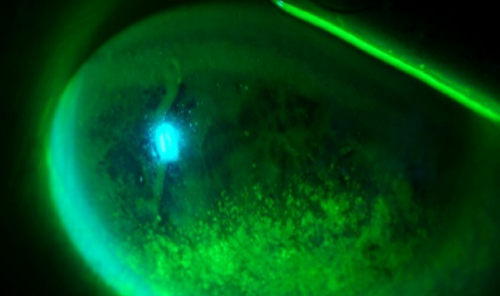

눈썹 찔림으로 인한 각막의 손상 여부 및 정도를 확인합니다.

각막 손상으로 인한 부정난시 등의 발생 여부와 시력저하가 있는지 확인합니다.

눈꺼풀 이상으로 인한 각막의 손상은 없는지 검사합니다.